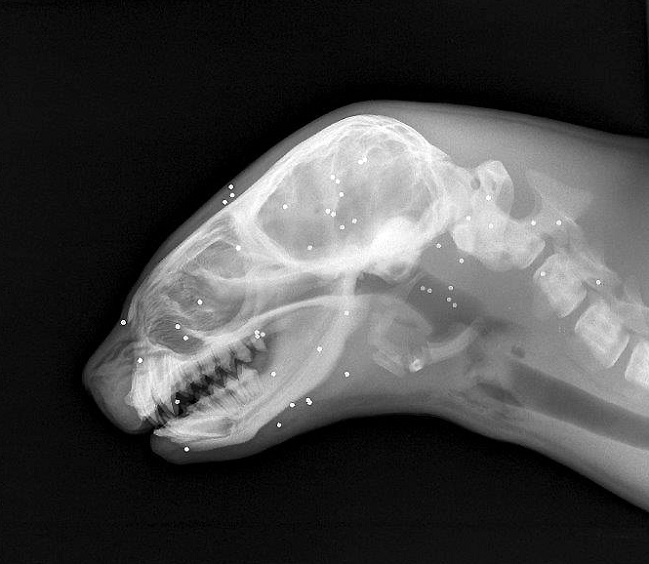

El animal había sido encontrado con múltiples lesiones en su cuerpo ocasionadas por disparos de escopeta: en total tenía 43 perdigones alojados.

"Se trató de una hembra, juvenil, que presentó múltiples perdigones en la cara, cabeza y cuello, presentando úlceras corneales en ambos globos oculares, lo que le generó ceguera", explicó la patóloga, Ana-Lía Henríquez.